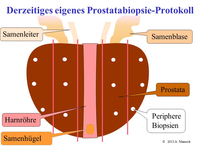

Die Methoden Ultraschall-Elastographie, der farbkodierte Doppler-Ultraschall sowie der kontrastmittelverstärkter Ultraschall und insbesondere die Echtzeit-MRT-Ultraschall-Fusion können helfen, auffällige Gebiete in der Prostata aufzuzeigen. So kann zum Beispiel ein in einer MRT (Magnetresonanztomographie) gefundener suspekter (also auffälliger) Bereich ganz gezielt biopsiert werden und auch zusätzlich noch elastographisch untersucht werden. Dies ist während einer herkömmlichen MRT-Untersuchung nicht möglich.

Eine multimodale Prostataabklärung erlaubt uns, die Prostata mittels modernster Verfahren zu untersuchen. Hierbei kommen verschiedene Untersuchungsmethoden zur Anwendung. Insbesondere die Echtzeitelastographie oder die kontrasmittelunterstützte Untersuchung der Prostata können hierbei wichtige Erkenntnisse über die Beschaffenheit der Prostata beisteuern. Auffällige Areale können in Echtzeit schmerzfrei mit lokaler Betäubung abgeklärt werden. Als Besonderheit können diese modernen Methoden auch mit einer bereits durchgeführten MRT-Untersuchung der Prostata fusioniert werden. Das bedeutet, in einer MRT gefundene auffälligen Areale der Prostata können zusätzlich mit modernsten Ultraschalluntersuchungen kombiniert untersucht werden und dann auch gezielt mittels gezielter Prostatabiopsie abgeklärt werden. Diese Untersuchung ist dann multimodal (zB Elastographie + konventionellem Ultraschall + MRT-Fusion).

Eine multimodale Prostataabklärung erlaubt uns, die Prostata mittels modernster Verfahren zu untersuchen. Hierbei kommen verschiedene Untersuchungsmethoden zur Anwendung. Insbesondere die Echtzeitelastographie oder die kontrasmittelunterstützte Untersuchung der Prostata können hierbei wichtige Erkenntnisse über die Beschaffenheit der Prostata beisteuern. Auffällige Areale können in Echtzeit schmerzfrei mit lokaler Betäubung abgeklärt werden. Als Besonderheit können diese modernen Methoden auch mit einer bereits durchgeführten MRT-Untersuchung der Prostata fusioniert werden. Das bedeutet, in einer MRT gefundene auffälligen Areale der Prostata können zusätzlich mit modernsten Ultraschalluntersuchungen kombiniert untersucht werden und dann auch gezielt mittels gezielter Prostatabiopsie abgeklärt werden. Diese Untersuchung ist dann multimodal (zB Elastographie + konventionellem Ultraschall + MRT-Fusion).

Zunächst einmal werden die bereits durchgeführten und von Ihnen mitgebrachten MRT-Bilder (1,5T-3T, mit/ohne rektale Spule, DICOM-Format) in unser Gerät eingelesen. Anschließend werden die suspekten Areale und die Organgrenzen der Prostata in der MRT-Bildgebung markiert. Nun beginnt der praktische Teil: In angenehmer Seitenlage wird über einen modernen transrektalen Ultraschall die Prostata aufgesucht und anhand der Anatomie der Prostata mit dem MRT Bild fusioniert. Der Untersucher sieht nun auf der linken Seite des Flachbildschirmes des Ultraschallgerätes das Original-MRT-Bild mitsamt des Markierungen und auf der korrespondierenden rechten Seite die Live Ultraschallbilder in denen die Markierungen der MRT-Untersuchung zu sehen sind. Die auffälligen Areale können nun einer Elastographie oder einer Kontrastmittel-Untersuchung unterzogen werden um den Grad der Auffälligkeit zu bestimmen. Auf Wunsch können auch jetzt gleich die Biopsien durchgeführt werden.

Folgende Untersuchungsarten sind möglich:

- Elastographie der Prostata

- Elastographie der Prostata mit gezielter Biopsie

- MRT-US-Fusion und Elastographie der Prostata mit Biopsie der Prostata